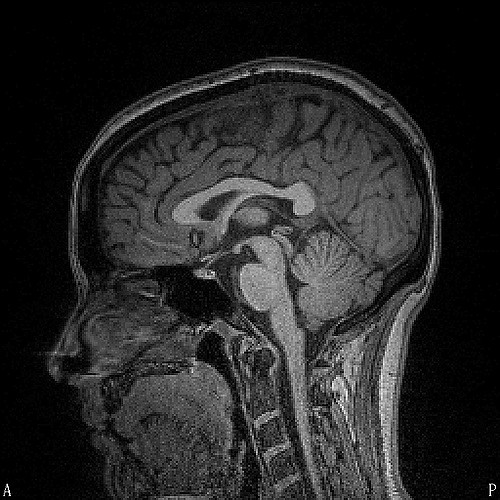

The Training Institute on Strangulation Prevention is hosting a webinar next month, Medical Imaging Protocols. The session will be held July 10th at 1pm ET. From the announcement:

This webinar features the Medical Advisory Board of the Training Institute on Strangulation Prevention, recognized as the leading experts in the field on non-fatal strangulation. These experts will be discussing new imaging recommendations they have developed and released for Emergency Room professionals.